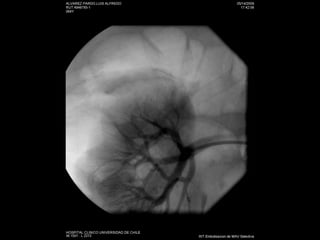

Angiografía

Stent y plastias de estenosis

Estudio No invasivo:AngioTC Doppler Angio RM: esclerosis sistémica nefrogénica Invasivo: angiografía

Stent y plastiasde estenosis